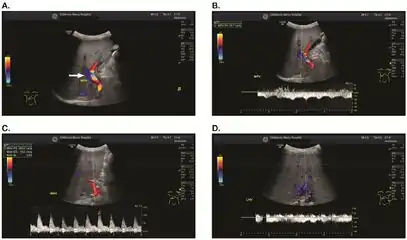

Doppler ultrasound of the liver is typically utilized to confirm or suggest the diagnosis. Common findings on liver doppler ultrasound include increased phasicity of portal veins with eventual development of portal flow reversal. The liver is usually enlarged but maintained normal echogenicity. A liver biopsy is required for a definitive diagnosis.

a-d) Individual who developed VOD/SOS after HCT for acute myelogenous leukemia